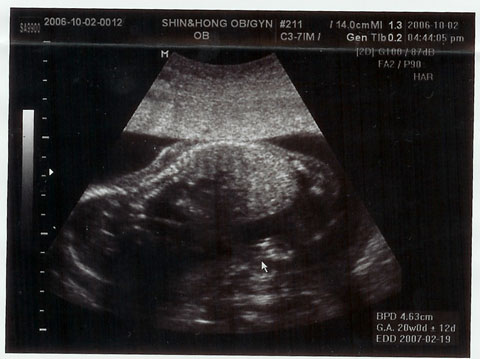

超音波写真もこのとおり。

2枚目の写真は、ひじから先の手。はっきり写ってるでしょ!

この日、

「20週まではプラス3キロ、そのあと40週までにプラス7キロですよ」

と釘を刺される。

いや、少なければ少ないほどいいんですけど…。元の体重が…。

そして、ダウン症などの可能性を見るための血液検査のため、

採血して終わり。

超音波写真プラス検査費用で、7万ウォンでした。

検査結果は1週間後に電話で、とのこと。

まさかとは思うけど…ちょっぴり心配になったのでした。

(18W3D)